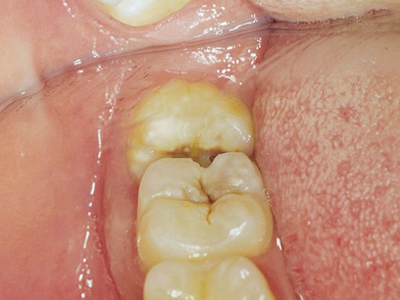

阻生牙是指由于邻牙、骨或软组织的阻碍而只能部分萌出或完全不能萌出,且以后也不能萌出的牙。引起牙阻生的成因,主要是由于颌骨缺乏足够的空间容纳全部恒牙。常见的阻生牙为下颌第三磨牙、上颌第三磨牙及上颌尖牙。

阻生牙可反复引起冠周炎,或引起邻牙牙根吸收和破坏,位置不正,不能完全萌出,好发部位是上、下颌第三磨牙。

对于阻生牙的处置需要首先明确阻生牙齿发育情况是否正常,对于由于早期外伤或其他原因造成发育异常,如牙根弯曲、短根等情况的阻生牙,还应根据患者的综合情况,决定牙齿是否保留。